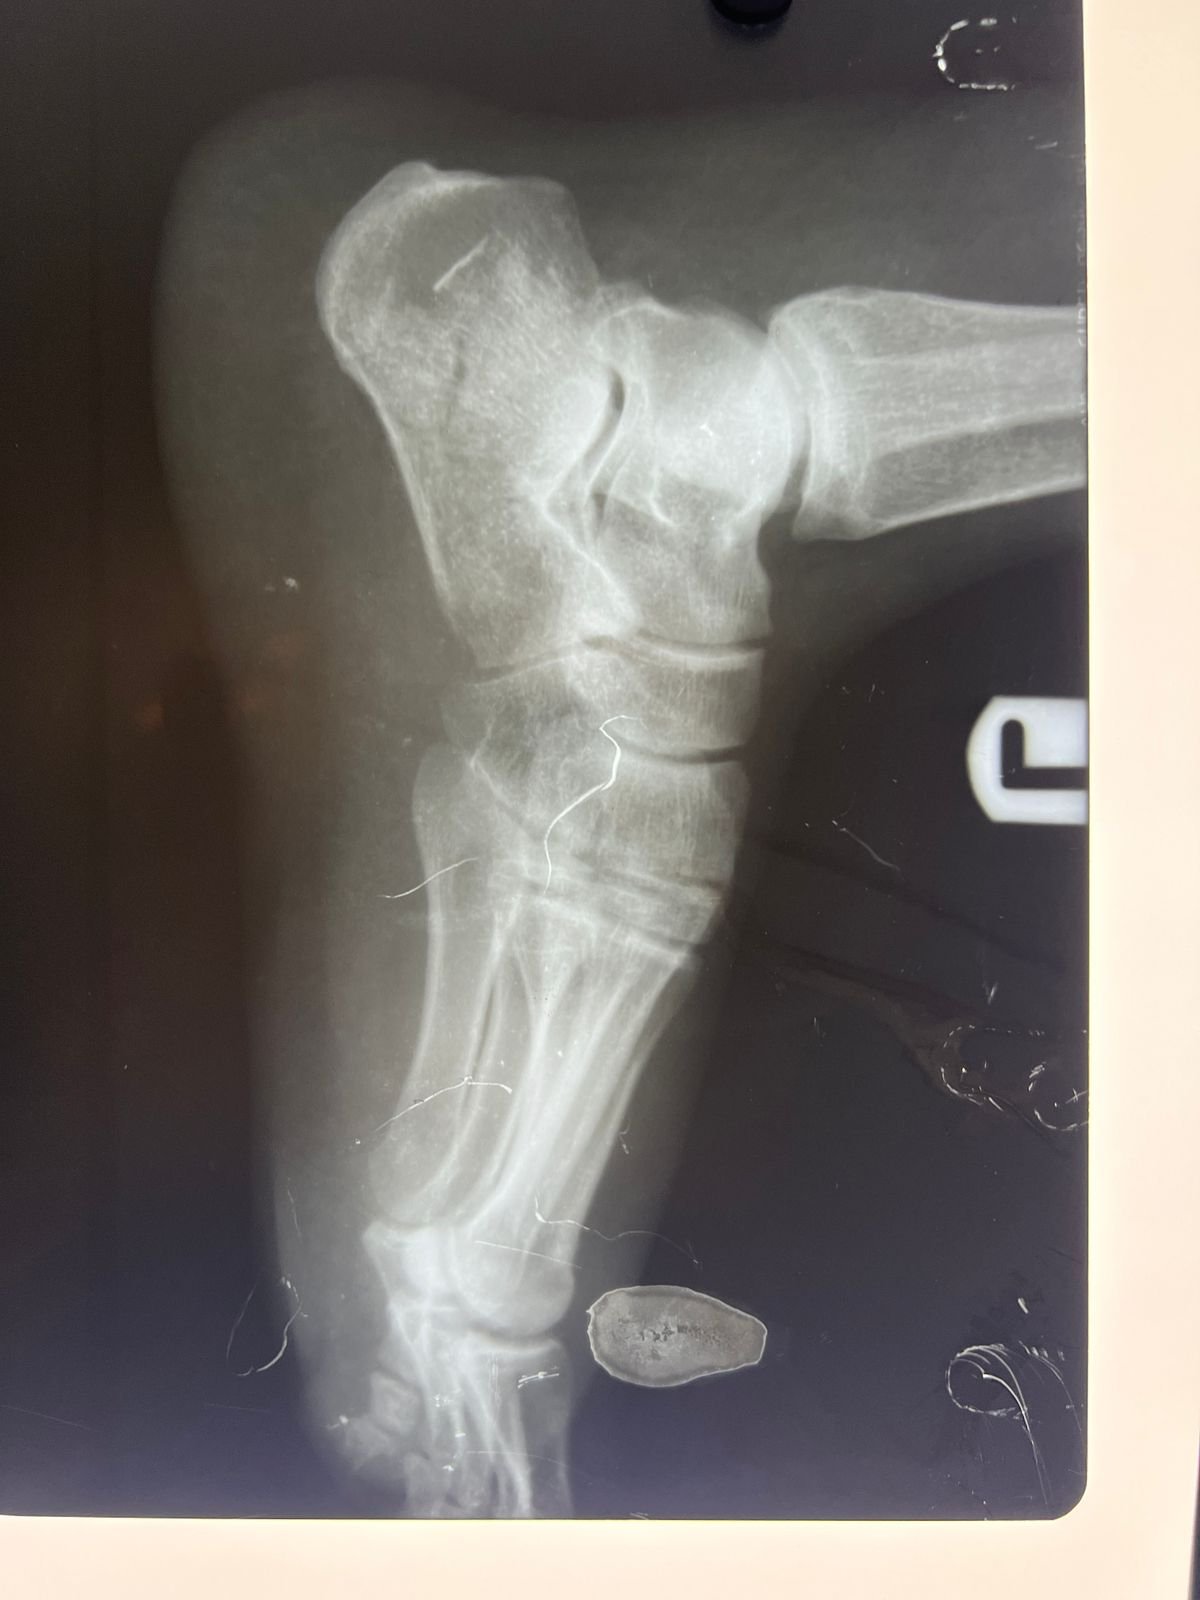

Heal fracture pre & postop | Clavicle fracture pre &

postop | Congenital foot deformity pre & post

plaster & operation | Total Hip replacement case |